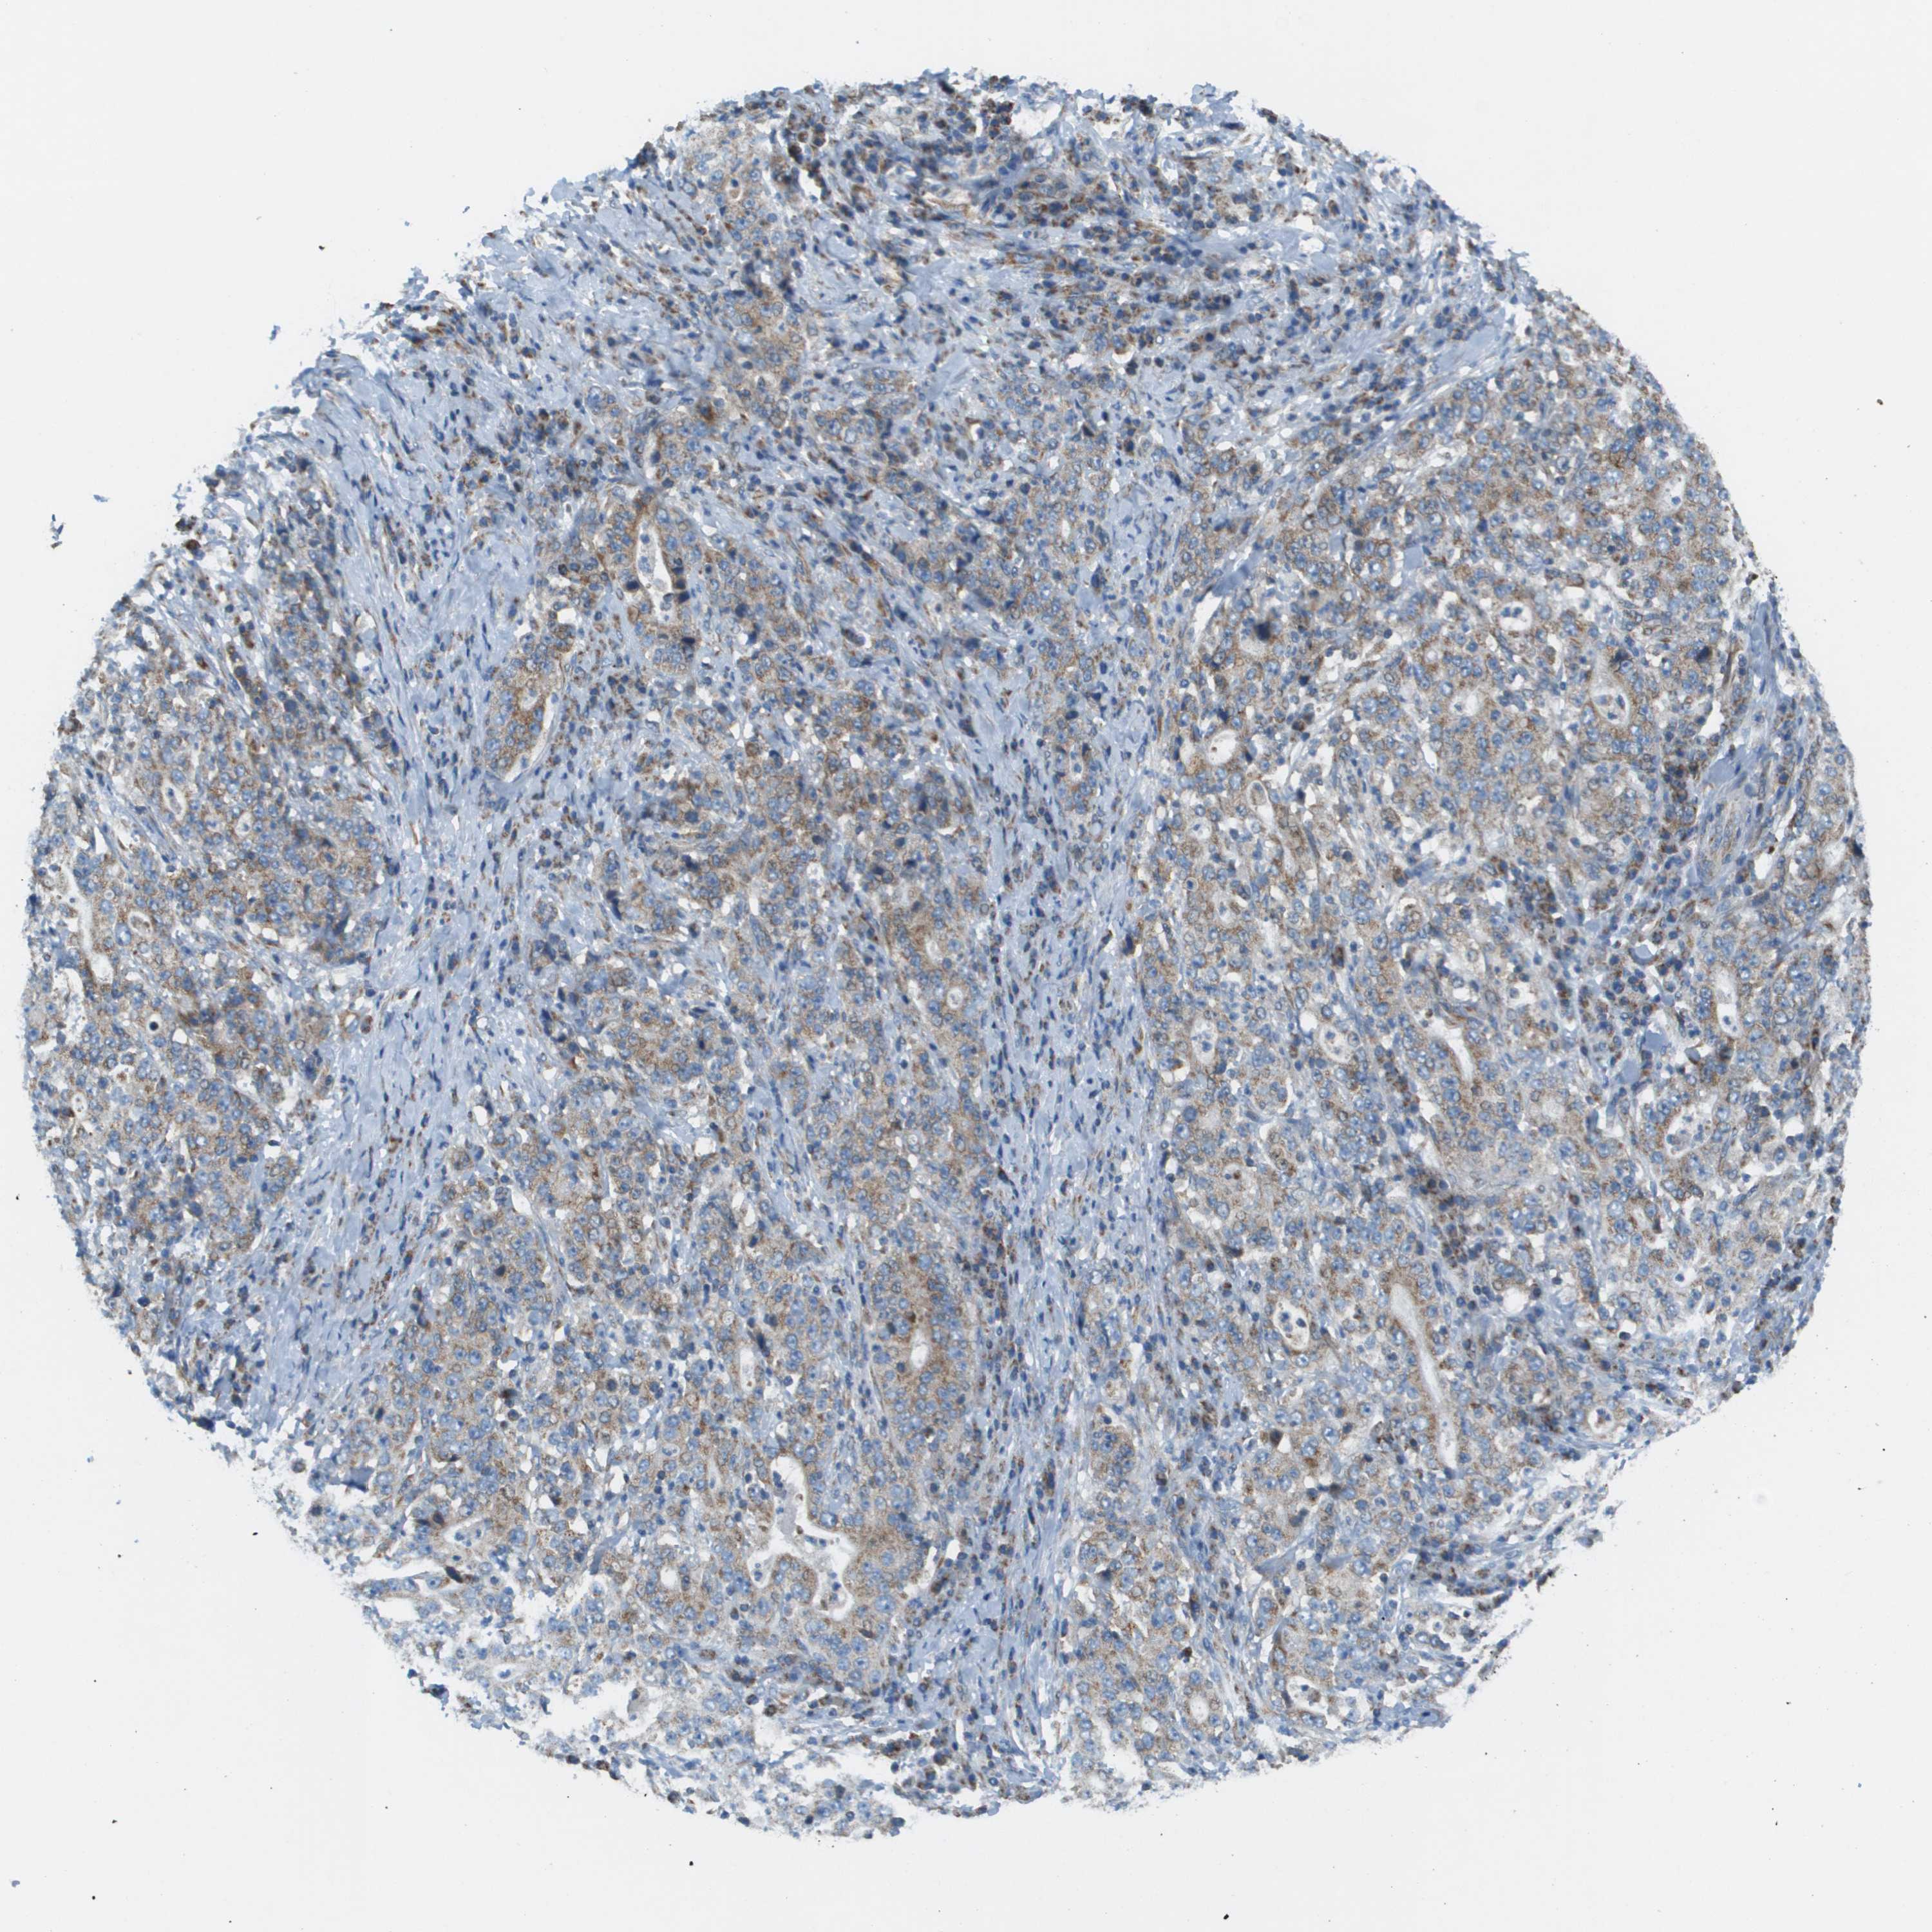

STOMACH CANCER - Protein expressioni

A mouse-over function shows sample information and annotation data. Click on an image to view it in a full screen mode. Samples can be filtered based on level of antibody staining by selecting one or several of the following categories: high, medium, low and not detected. The assay and annotation is described here.

Antibody stainingi

Antibody staining in the annotated cell types in the current human tissue is reported as not detected, low, medium, or high, based on conventional immunohistochemistry profiling in selected tissues. This score is based on the combination of the staining intensity and fraction of stained cells.

Each image is clickable and will lead to virtual microscopy that enables deeper exploration of all samples and also displays staining intensity scores, fraction scores and subcellular localization as well as patient and tissue information for each sample.

Antibody HPA017160

Staining

High

Medium

Low

Not detected

Intensity

Strong

Moderate

Weak

Negative

Quantity

>75%

75%-25%

<25%

None

Location

Nuclear

Cytoplasmic/membranous

Cytoplasmic/membranous,nuclear

Adenocarcinoma, NOS